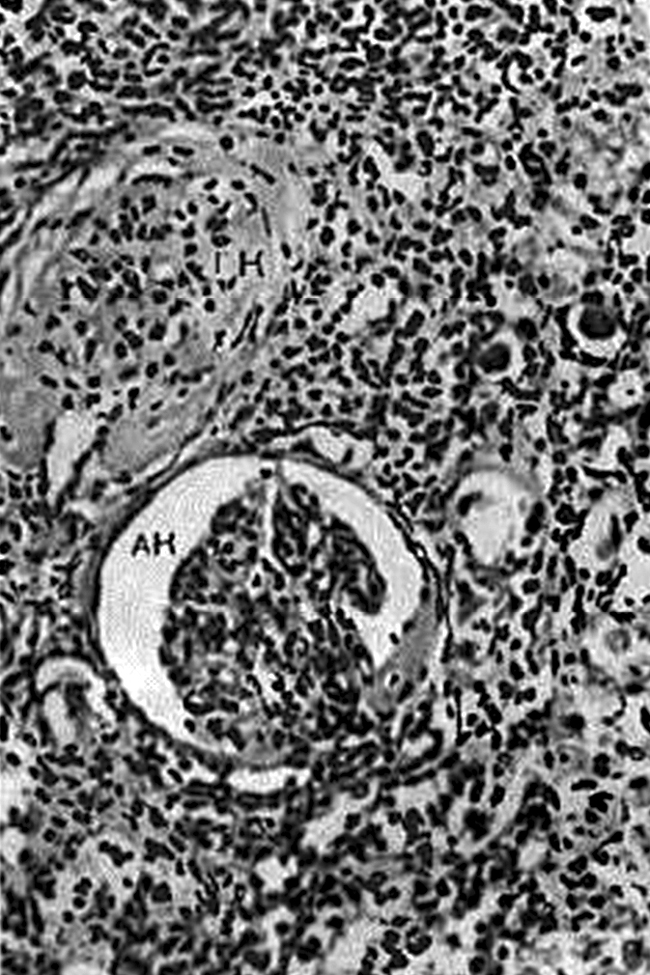

Почечная форма. При хроническом течении гипертонической болезни развивается артериолосклеротический нефросклероз (рис. 8), связанный с гиалинозом приносящих артериол. Уменьшение притока крови приводит к атрофии и гиалинозу соответствующих клубочков. Их функцию выполняют сохранившиеся клубочки, которые подвергаются гипертрофии.

Поэтому поверхность почек приобретает зернистый вид: гиалинизированные клубочки и атрофированные, склерозированные нефроны западают, а гипертрофированные клубочки выступают над поверхностью почек (рис. 7, в; рис. 8). Постепенно склеротические процессы начинают преобладать, и развиваются первично-сморщенные почки. При этом нарастает хроническая почечная недостаточность, которая завершается уремией.

Рис. 8. Артериолосклеротический нефросклероз. Гиалинизированный (ГК) и атрофирующийся (АК) клубочки